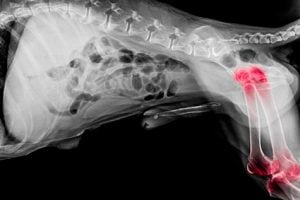

L’arthrose est la détérioration du cartilage articulaire. Tous les chiens peuvent être atteints d’arthrose. Cette maladie ne peut pas être guérie mais on peut soulager la douleur qu’elle entraîne.